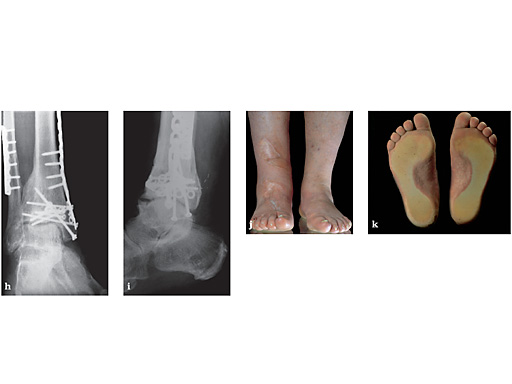

hi X-rays after 4 years.

jl Functional pictures after 4 years.